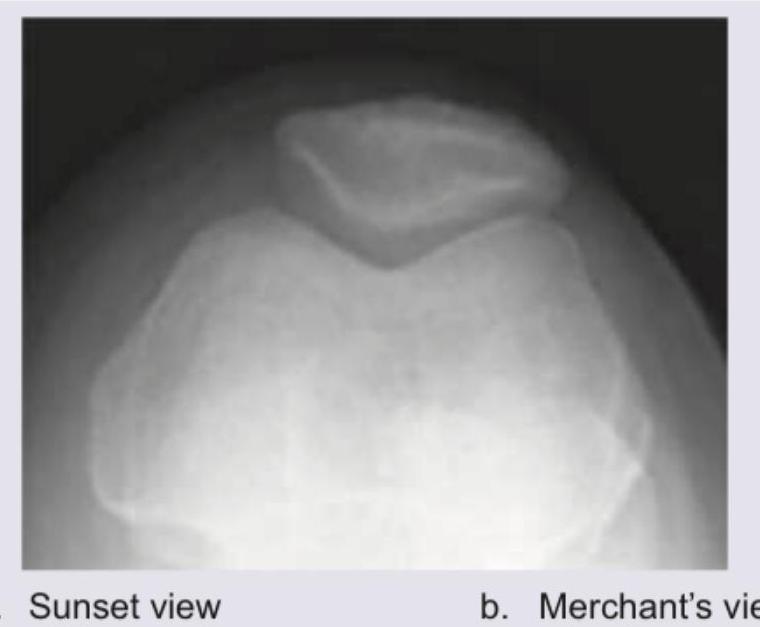

The following view of the knee joint is known as:

Explanation: ***Sunset view*** - Also known as the **skyline view** or **tangential view** of the patella, this view is taken with the knee flexed (typically 30–60°), allowing visualization of the **patellofemoral joint space** in axial projection. - It is excellent for diagnosing **patellar tracking issues**, patellar fractures, **chondromalacia patellae**, and assessing the patella's articulation with the **femoral trochlea**. *Merchant's view* - The Merchant's view is another tangential axial view of the patella, performed with the patient **supine and the knees flexed at 45°** over the edge of the table with the X-ray beam angled caudally. - While it also visualizes the **patellofemoral joint**, the patient positioning and beam angulation differ from the standard sunset/skyline view. *Tunnel view* - Also called the **notch view** or **intercondylar view**, this is a PA projection with the knee flexed at 40–50°, used to visualize the **intercondylar notch** and posterior femoral condyles. - It is primarily used to detect **osteochondral defects**, loose bodies in the notch, and **osteochondritis dissecans**. *Rosenberg view* - The Rosenberg view is a **weight-bearing PA view** taken with the knee flexed at 45°, used to assess **joint space narrowing** in the posterior tibiofemoral compartment. - It is more sensitive than a standing AP view for detecting **early osteoarthritis** of the knee.